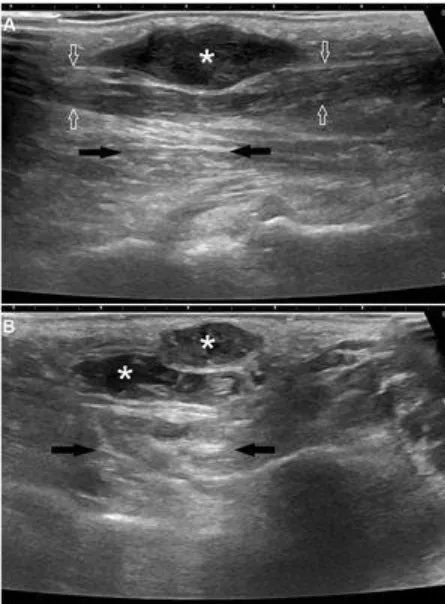

Esta comunicación breve de la Revista Radiología expone la presentación de un linfoma como neurolinfomatosis de los nervios ciático y mediano ¡No te lo pierdas! 🔗 bit.ly/45cmiUi

Esta comunicación breve de la Revista Radiología expone la presentación de un linfoma como neurolinfomatosis de los nervios ciático y mediano

¡No te lo pierdas! 🔗 bit.ly/45cmiUi